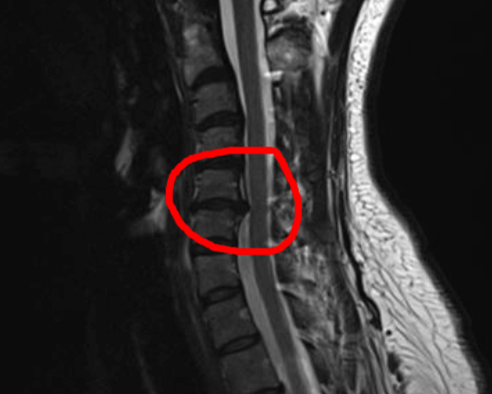

My MRI was of my head as well as my Cervical C-spine. This is the report:

The one alternative option Dr Tollesson provided, was a cortisone injection, which would give me about 6 months relief but, quite frankly, it didn’t sound like a solution. He then offered a surgical procedure called Anterior cervical discectomy fusion or “ACDF C5/6”. Use this to search on YouTube, if you’d like to see videos of the procedure.

He recommended surgery based on the contact with the nerve root, which is causing pain down both arms and legs. He also explained that the head is quite a weight in, and of, itself. Therefore, when you have the issue I do (Common amongst many), it’s added pressure on the neck and that area.